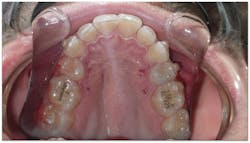

- He measured 28 mm, which is very narrow considering that uncrowded adults measure 35 mm–39 mm.

- His narrow maxilla had a corresponding vaulted palate, which is clearly visible (figure 3).